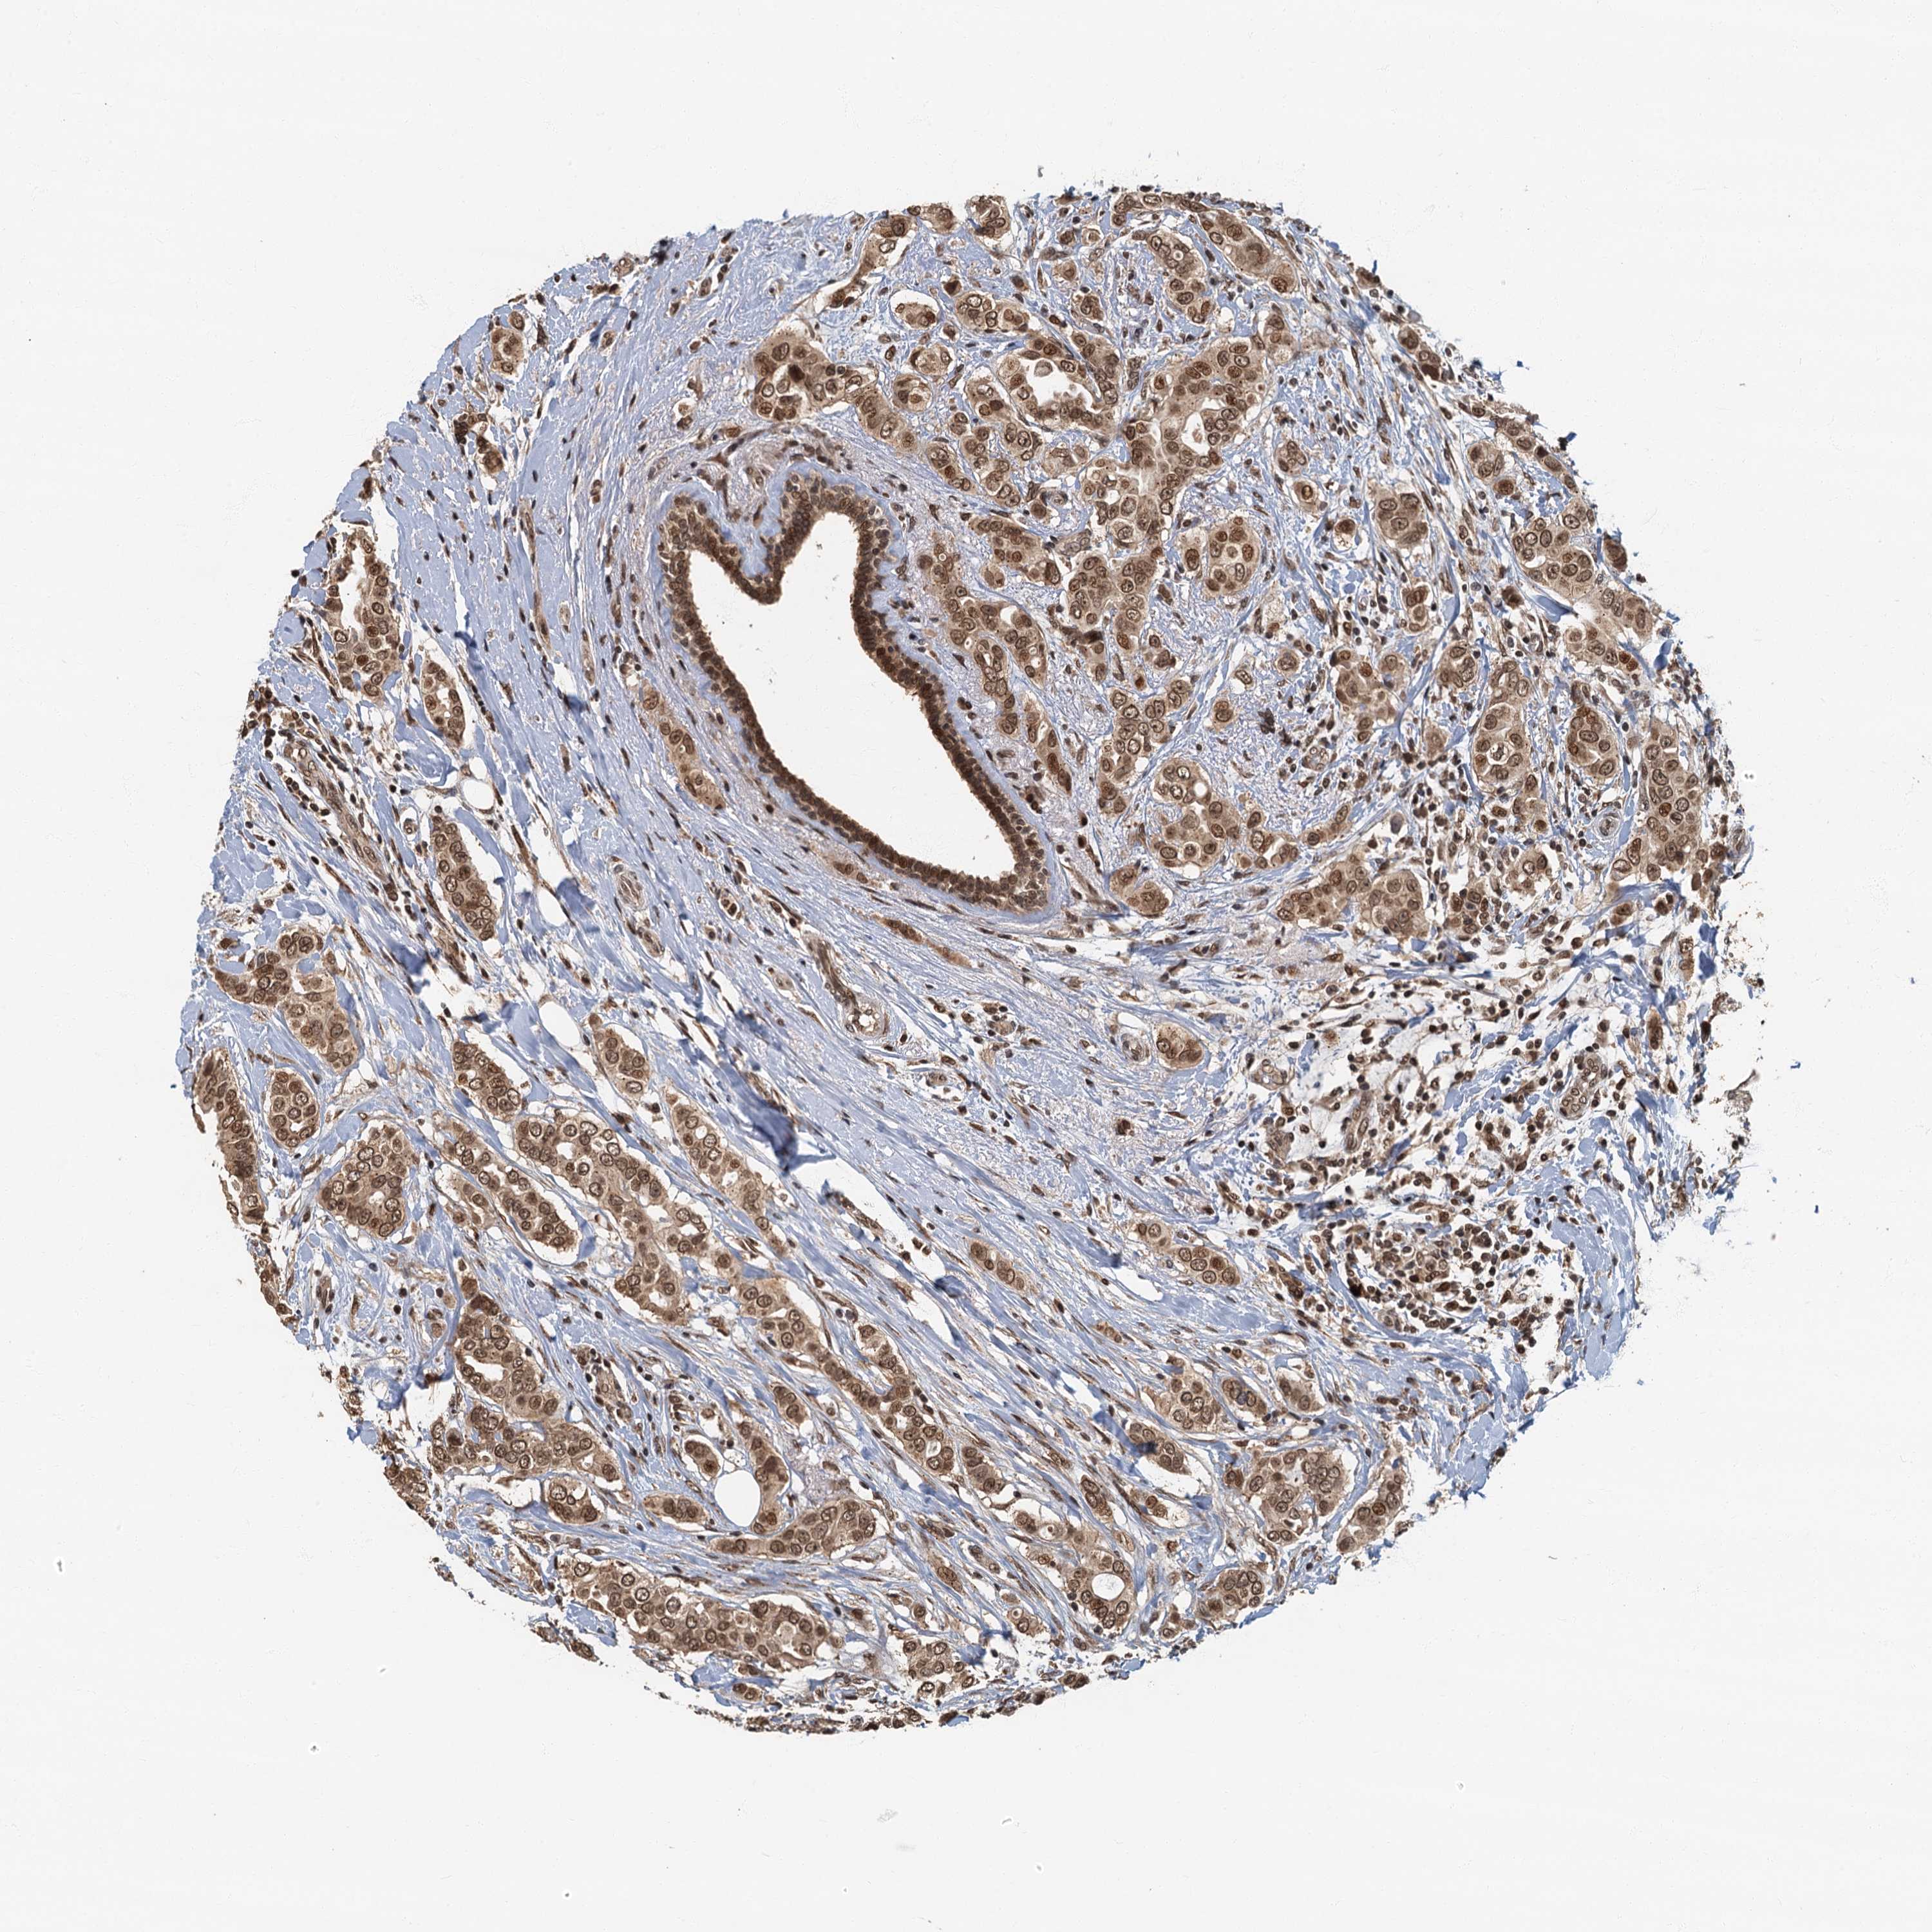

CANCER BREAST CANCER Show tissue menu

BRCA TCGA BRCA VALIDATION PROTEIN EXPRESSION